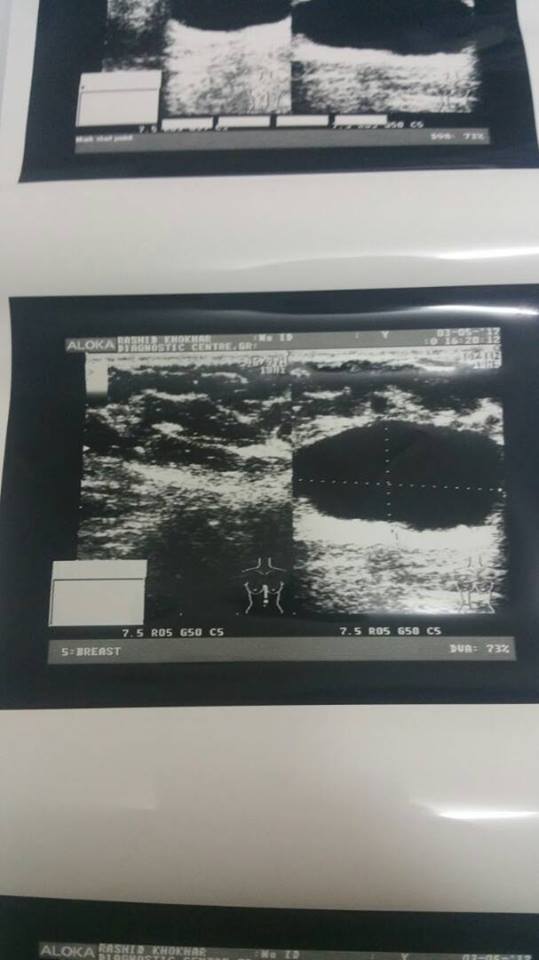

The best idea for u would be to go see a breast surgeon and likely get an

FNAC done for the nodular mass .. hopefully it shouldn't be anything but

just to be on the safe side better to get it investigated.